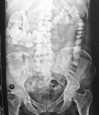

Transmigration and spontaneous passage of a gossypiboma documented on contrast study

Gossypiboma or textiloma is a rare but very unfortunate complication of surgery. It refers to a retained foreign body usually forgotten within the abdominal cavity at the end of an operation. It may be a surgical sponge, gauze pad or other form of textile. We present the case of a middle aged lady who following cholecystectomy had a forgotten gauze which underwent transmural migration and was later expelled via the rectum demonstrated by radiological studies.